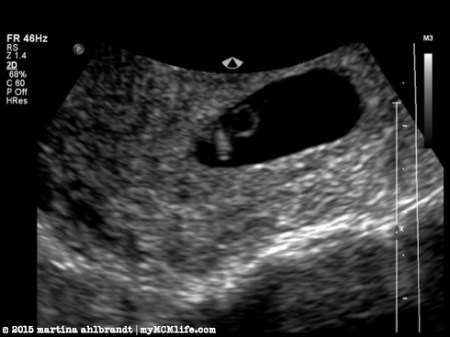

My first ultrasound was at about 6.5 weeks. We could see the baby’s heart beating but he or she was a little too small to measure accurately so they had us come back 2 weeks later. Also, at this point the ultrasound tech saw “a flicker of something else” that our doctor said could be an identical twin. Or could be just an ultrasound blip. Because it was so small it was hard to tell for sure.